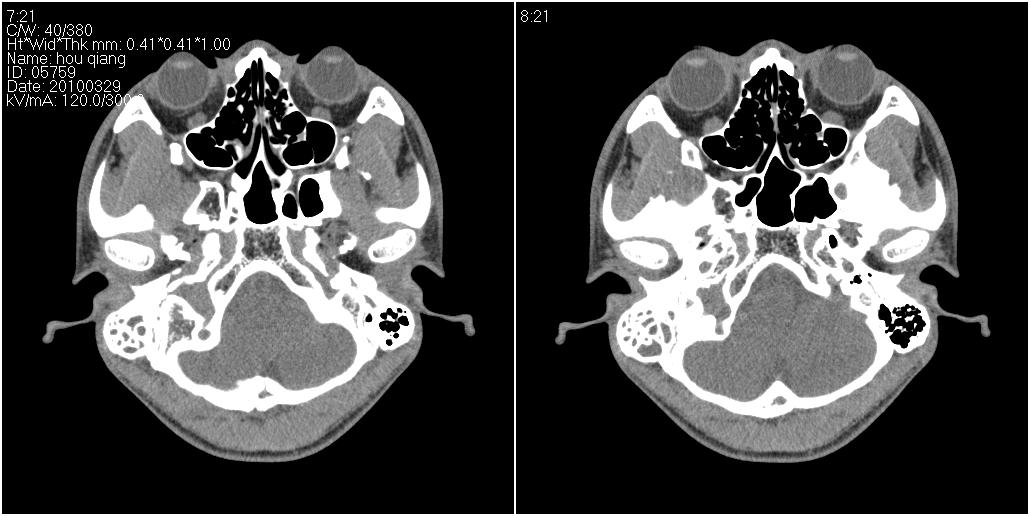

标题: CT25419:男性,18岁。右耳肿、痛5个多月。 [打印本页]

标题: CT25419:男性,18岁。右耳肿、痛5个多月。

中耳炎 中耳肿物 活检吧

右侧中耳乳突炎累及外耳道,鼻咽腺样体肥大。

1)右侧慢性中耳乳突炎并右侧中耳腔及外耳道肉芽肿或胆脂瘤形成。2)鼻咽腺样体肥大。